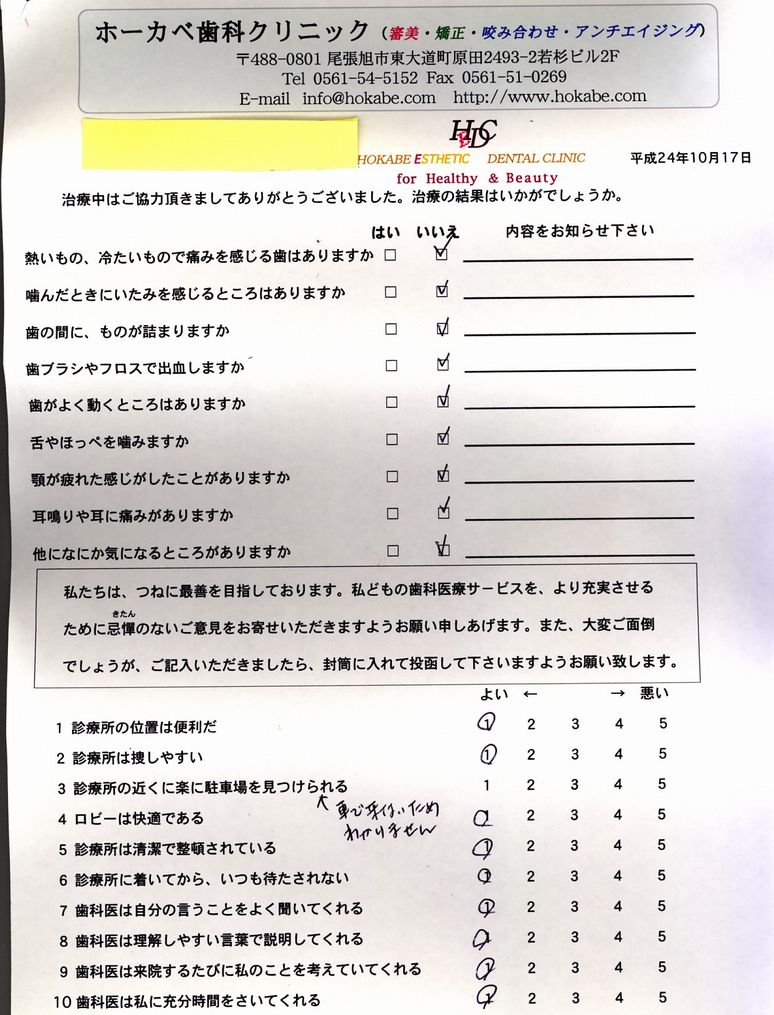

ホーカベ歯科クリニック 歯科医師 波々伯部重俊